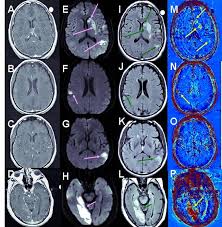

Analyzing The Blood Brain Barrier The Benefits Of Medical Imaging In Research And Clinical Practice Sciencedirect

Analyzing The Blood Brain Barrier The Benefits Of Medical Imaging In Research And Clinical Practice Sciencedirect from ars.els-cdn.com

The Application Of Mri For Depiction Of Subtle Blood Brain Barrier Disruption In Stroke

The Application Of Mri For Depiction Of Subtle Blood Brain Barrier Disruption In Stroke from www.ijbs.com